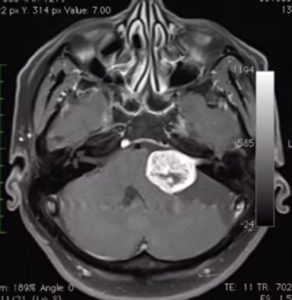

磁力共振影像診斷

磁力共振醫學影像檢查,有助於明確診斷及鑑別小腦腦橋角區域的腫瘤,例如腦膜瘤、表皮樣囊腫、三叉神經鞘瘤等的鑑別。

聽覺神經瘤的磁力共振影像特點:

腫瘤對小腦、腦幹的壓力。

可見聽覺神經瘤由內聽道向內側長出來,像蝌蚪的尾巴一樣。